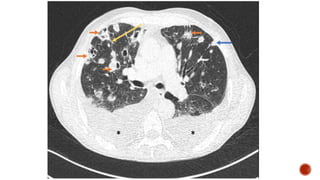

Frontal chest radiograph shows few ill defined patchy opacities in both the lung

fields, few of them showing cavitatory changes. TCC seen in situ.

Compared to the previous radiograph there is reduction in the number of opacities

with cavitatory changes.

 Malignancy:

 Squamous cell carcinoma of the lung

 Metastasis :

 squamous cell ca

 adenoca from GIT/breast

 sarcoma

 cervical carcinoma

 urothelial carcinoma of the bladder

 Infection :

 Septic embolism

 Pulmonary tuberculosis

 Abscess

 Post pneumonic pneumatocele

 Necrotizing pneumonia

 Autoimmune :

 Wegeners granulomatosis

 Rheumatoid nodules

 Distribution :

 Peripheral

 Lower lobe predominance

 Multiple

 Bilateral

 Varying stages of cavitation

 Feeding vessel sign